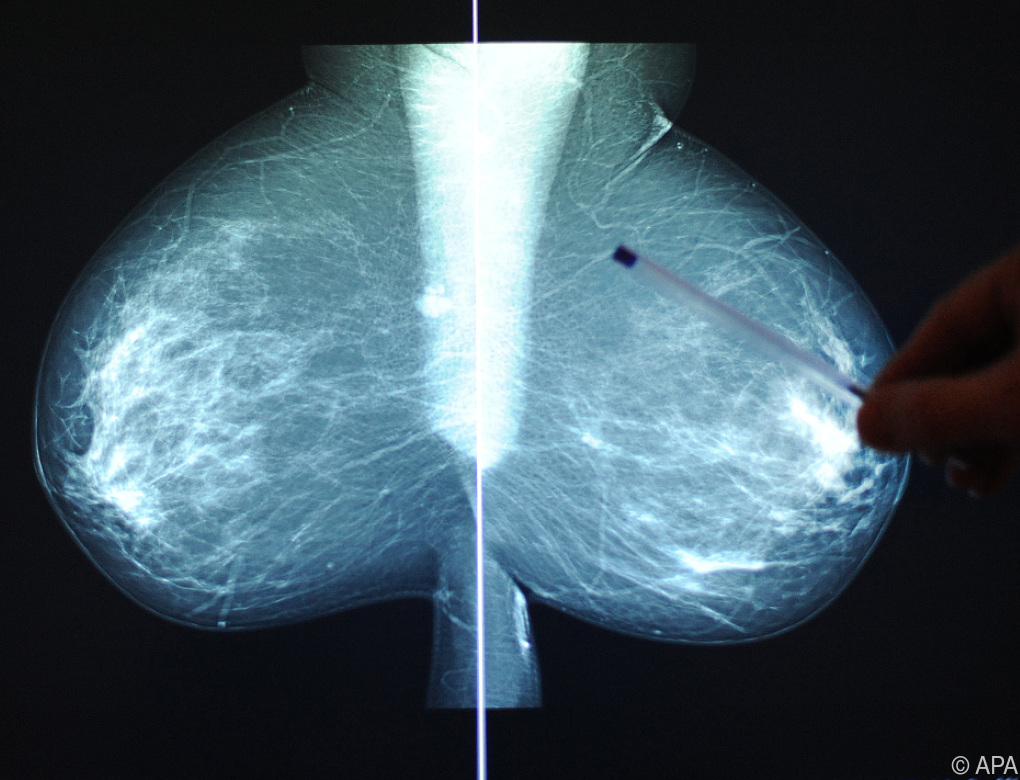

Die Geschichte reicht bis in den Herbst 2018 zurück. Bei einer Routineuntersuchung wurden damals verdächtige Mikroverkalkungen in der Brust festgestellt, die eine eingehendere diagnostische Abklärung erforderten. Die Patientin unterzog sich daraufhin einer Mammabiopsie. Die Entnahme der Proben erfolgte in den Ambulanzen der USL Euganea, während die histologische Untersuchung in den Labors des Krankenhausverbunds durchgeführt wurde. Das Ergebnis lautete „infiltratives duktales Karzinom dritten Grades“ – eine aggressiv und fortgeschritten geltende Form des Brustkrebses, die einen sofortigen Eingriff erforderte. So wurde der Frau am 21. November desselben Jahres in einer Klinik in Abano Terme die linke Brust vollständig entfernt.

Bei den gerichtsmedizinischen Untersuchungen fällt eine technische Unstimmigkeit ins Auge: Die Diskrepanz zwischen den 14 Gewebeproben, die bei der ursprünglichen Biopsie entnommen wurden, und den nur fünf Proben, die der Pathologe, der den Krebs diagnostiziert hatte, analysiert hatte. „Die Unstimmigkeit zwischen der Menge des bei der Biopsie entnommenen Materials und dem, was dem Pathologen zur Untersuchung vorgelegt wurde, ist offensichtlich”, betont Rechtsanwältin Da Ruos und verweist dabei auf die Analysen, die zum Antrag auf den Gentest führten.